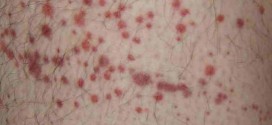

La púrpura. Afección caracterizada por la formación de manchas rojas o azuladas en la piel constituidas por diminutos extravasados sanguíneos subcutáneos de hemorragia de eritrocitos en la piel o en mucosas que provoca la aparición de pequeñas manchas rojas. La púrpura suele estar causada por algún tipo de crisis sanguínea (trombopenia), sintomas de enfermedades diversas o traumatismos. Pues bien una …